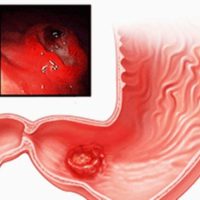

Aktiválja az emésztőrendszert. Belép a szervek a gyomor-bél traktus a hasnyálmirigy. Abban az esetben hiányzik a gasztrin megfigyelt tünetek az emésztőrendszer.

Jogsértések hormontermelés és azok következményei

Nem sikerült hiánya miatt a hasnyálmirigy hormon fejleszt különböző okok miatt. Gyakran az egyik fő kiváltó tényezők közé tartozik a veleszületett szervi hibák a szerkezet. Nem az inzulin növekedéséhez vezet az összeg glukagon és csökkenti a vércukorszintet. Ezeket a folyamatokat kíséri növekedése adrenalin.

Hiánya az inzulin és a túlzott glükagonsze okozzák az olyan megbetegedéseket, mint a hipoglikémia. A felesleges inzulin kíséri fejlődését hasnyálmirigy inzulinómát. Ezt a betegséget az jellemzi, jóindulatú daganatok. Gátlási hiányával szomatosztatin provokál belső funkcióinak a test, ami elnyomása rögzített és a metabolikus folyamatok.

Amennyiben a termelés aktív komponensek más meghibásodást észlel a mirigy. Még nagyobb a kockázata a cukorbetegség kialakulásának és autoimmun reakciókat. A nagy valószínűséggel súlyos következményei vannak, mint a alulműködése vagy túlműködése a hatóság.

A hasnyálmirigy egy fontos része az emésztőrendszer. Ez felelős a hormonok és enzimek, amelyek szabályozzák az emésztést és a tápanyagok beépülését. Gátlása szervi funkciók vezet hibás működését az emésztőrendszer, nagy valószínűséggel a fejlődő megbetegedések.